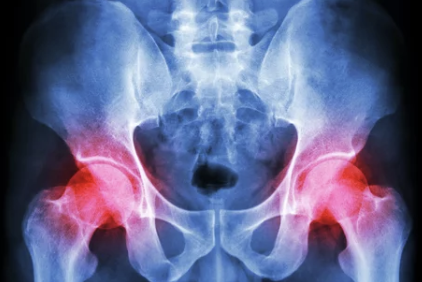

2) 관절염

- 퇴행성 관절염(골관절염): 연령 증가로 인해 고관절의 연골이 닳아 통증과 뻣뻣함이 발생.

- 류마티스 관절염: 면역체계 이상으로 인해 관절에 염증이 생기며, 고관절을 포함한 다발성 통증이 나타남.

3) 영상검사

- X-ray: 골절, 관절염 등 뼈 문제를 확인.